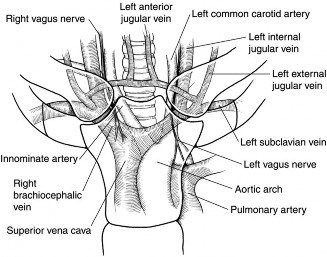

The correct answer is (D). One of the functions of the rotator cuff is to dynamically stabilize the humeral head in the glenoid, providing a fulcrum so that the shoulder can articulate properly. In order to do this, forces around the center of rotation must be equal in the transverse and coronal planes. In the transverse plane, the humeral

head is relatively unconstrained by the glenoid anteriorly and posteriorly. Any anterior and posterior forces placed on the humeral head must be balanced so that it does not sublux or dislocate in an anterior or posterior direction. This is accomplished by the subscapularis pulling the humeral head anteriorly with the same force that the infraspinatus and teres minor pull it posteriorly. All of these muscles also act to pull the humeral head medially into the concavity of the glenoid, stabilizing it in a medial-lateral dimension. When a patient has a rotator cuff tear, these force couples become uneven and can lead to instability (see Fig. 2–7).

Figure 2–7A. The transverse plane force couple (left) and the coronal plane force couple (right) are disrupted by a massive rotator cuff tear involving the posterior rotator cuff, infraspinatus, and teres minor. B. An alternative pattern of disruption of the transverse plane force couple. The transverse plane force couple is disrupted by a massive tear involving the anterior rotator cuff (ie, subscapularis). D = deltoid, I = infraspinatus, O = center of rotation, S = subscapularis, TM = teres minor. (From Burkhart SS, Lo IKY. Arthroscopic rotator cuff repair. J Am Acad Orthop Surg. 2006;14(6):333–346.)

The correct answer is (C). As stated above, the rotator cuff is needed to stabilize the humeral head in the glenoid and provide a fulcrum to allow the humeral head to

rotate properly. In the coronal plane, the humeral head is relatively unconstrained by the glenoid superiorly and inferiorly, so forces on the humeral head in these directions must be balanced. This is accomplished by the combined inferior forces of the subscapularis, infraspinatus, and teres minor equaling the superior force of the deltoid. When a patient has a rotator cuff tear, these force couples can be uneven, causing instability (see Fig. 2–7 above). Objectives: Did you learn...? Classify full-thickness rotator cuff tears based on size, shape, and retraction? Identify the rotator cable and crescent?